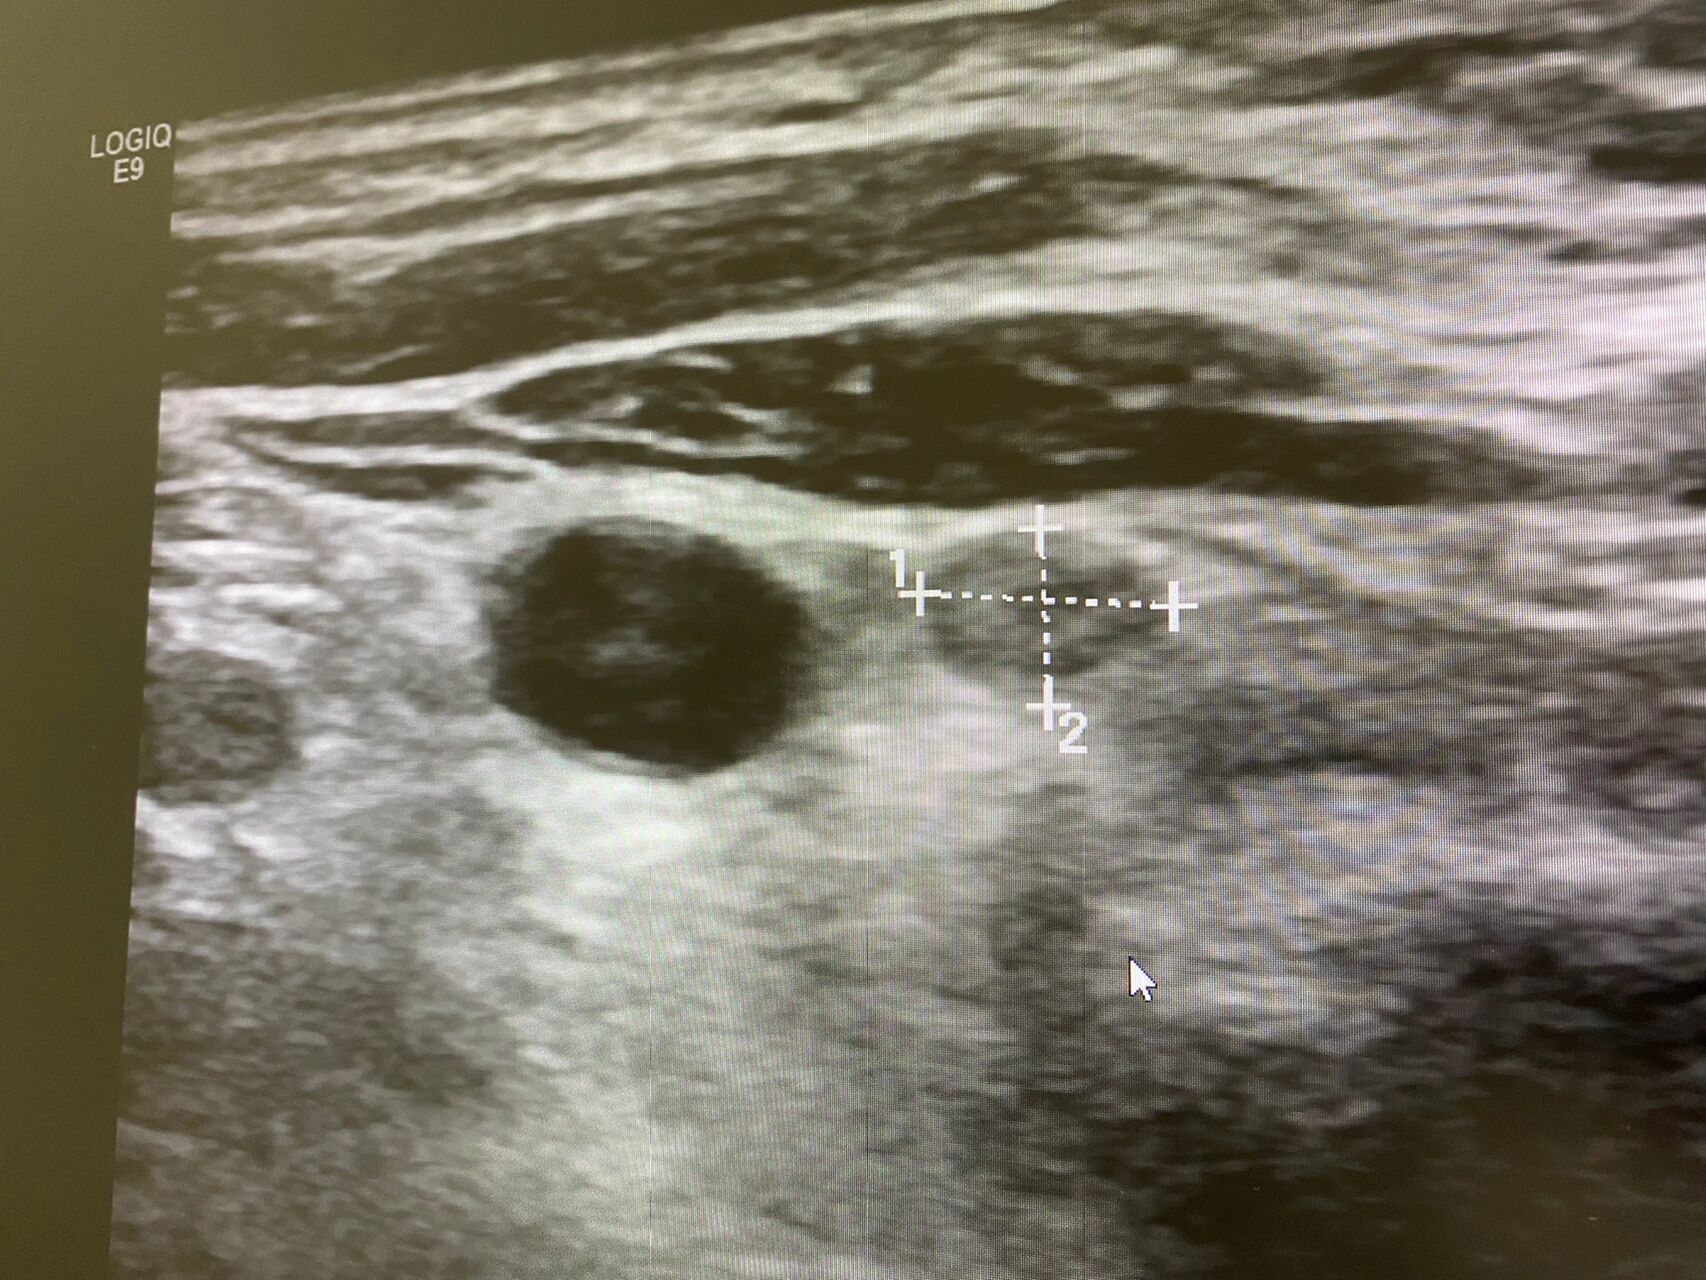

b超显示腋下有淋巴结

记录一个b超观察下的淋巴结